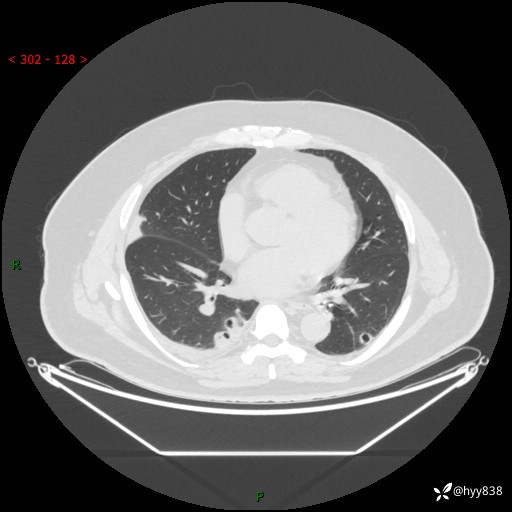

病例中年男性,发热来诊。典型?鉴别疾病谱有哪些,下一步---结果公布~

性别:男

年龄:48岁

简要病史:发热来诊(门诊病人)

胸部CT平扫